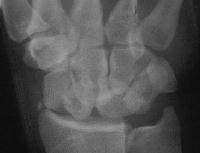

Case 5. Another,same bidirectional technique. Here, I ran the second screw too close to the first, and may have flattened the leading threads - not

ideal. The preop status:

Click for larger image